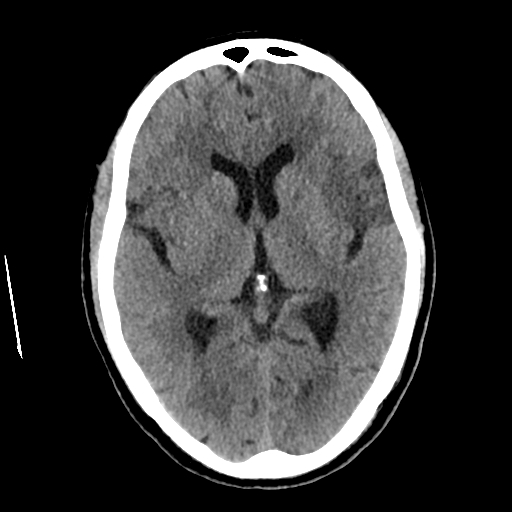

Se presenta el caso de un paciente masculino de 62 años que acudió al servicio de emergencia por inicio súbito de debilidad en el hemicuerpo derecho, dificultad para articular palabras y desviación de la comisura labial, síntomas de pocas horas de evolución, por lo que se sospechó evento vascular cerebral agudo y se solicitó tomografía cerebral simple de urgencia.

La tomografía evidenció una zona de hipodensidad corticosubcortical localizada en la región frontal posterior izquierda, con extensión hacia el opérculo frontal y región insular ipsilateral, asociada a discreto borramiento de surcos corticales en dicha región, hallazgos compatibles con evento vascular cerebral isquémico agudo en territorio de la arteria cerebral media izquierda.

No se identificaron signos de hemorragia intracraneal ni colecciones extraaxiales al momento del estudio, hallazgo relevante para la toma de decisiones terapéuticas iniciales.

Adicionalmente, se observaron cambios crónicos asociados a enfermedad de pequeños vasos cerebrales, manifestados por hipodensidad periventricular sugestiva de leucoaraiosis, así como un evento lacunar isquémico crónico en la cápsula externa izquierda, indicativo de daño vascular previo. También se documentaron calcificaciones ateroescleróticas en arterias intracraneales y cambios degenerativos cervicales propios de la edad.